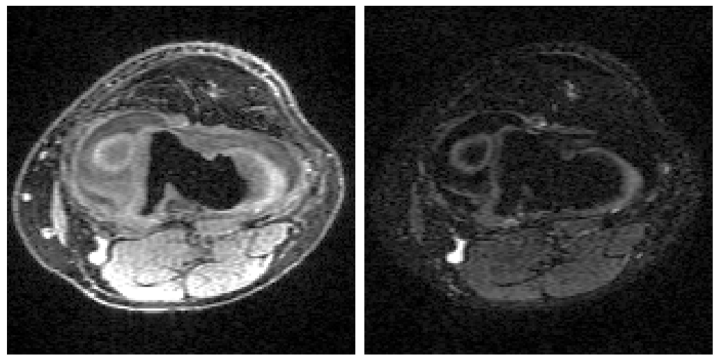

Magnetic resonance imaging (MRI) exam protocols consist of multiple contrast-weighted images of the same anatomy to emphasize different tissue properties. Due to the long acquisition times required to collect fully sampled k-space measurements, it is common to only collect a fraction of k-space for each scan and subsequently solve independent inverse problems for each image contrast. Recently, there has been a push to further accelerate MRI exams using data-driven priors, and generative models in particular, to regularize the ill-posed inverse problem of image reconstruction. These methods have shown promising improvements over classical methods. However, many of the approaches neglect the additional information present in a clinical MRI exam like the multi-contrast nature of the data and treat each scan as an independent reconstruction. In this work we show that by learning a joint Bayesian prior over multi-contrast data with a score-based generative model we are able to leverage the underlying structure between random variables related to a given imaging problem. This leads to an improvement in image reconstruction fidelity over generative models that rely only on a marginal prior over the image contrast of interest.

Brett Levac, Ajil Jalal, Jon Tamir

2023 IEEE 20th International Symposium on Biomedical Imaging (ISBI) 2023